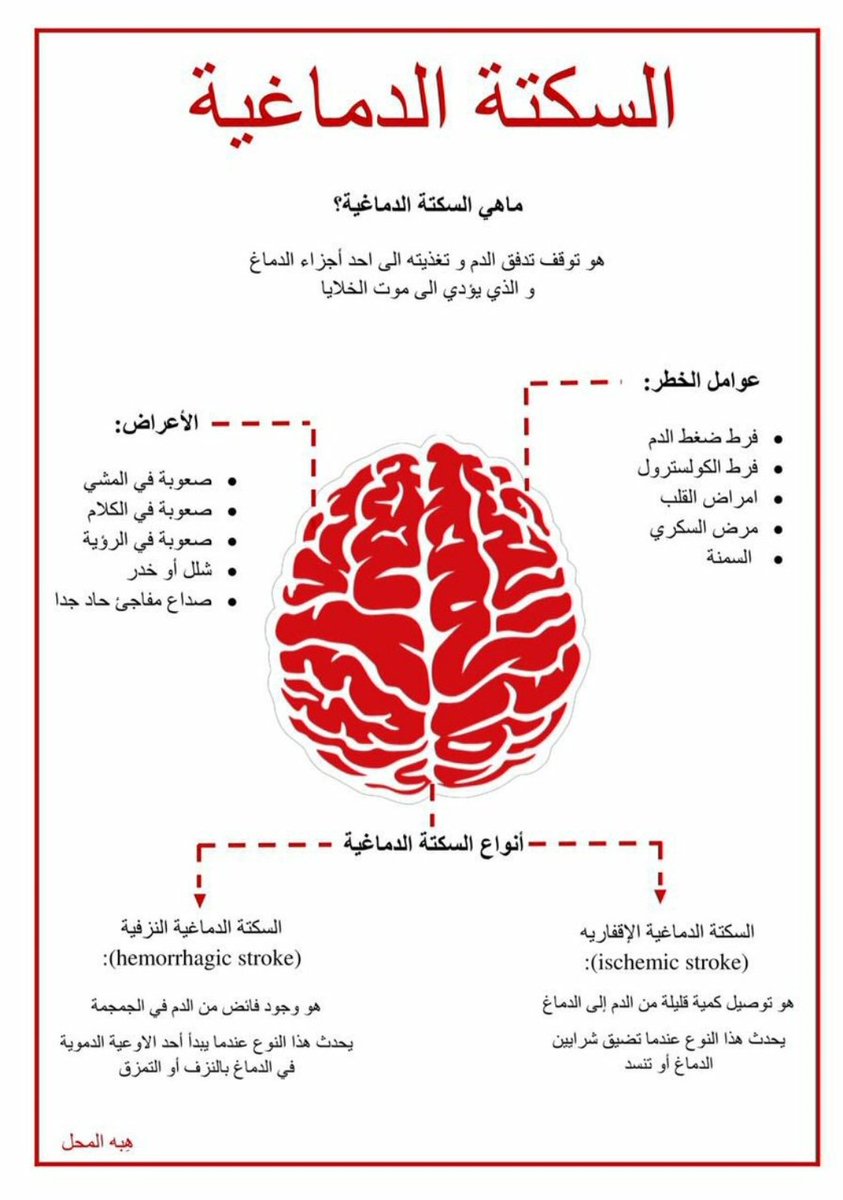

💥هي نقص ترويه الدم (الاوكسجين) لمنطقه بالمخ اوالحبل الشوكي اوشبكية العين

💥انواعها(اقفاريه ونزفيه)

💥انواعها(اقفاريه ونزفيه)

💥أعراض #السكته_الدماغيه بنوعيها

💥عوامل الخطورة

🧠ارتفاع الضغط

🧠السكري

🧠الكوليسترول

🧠التدخين

🧠قلة النشاط البدني

🧠أمراض القلب